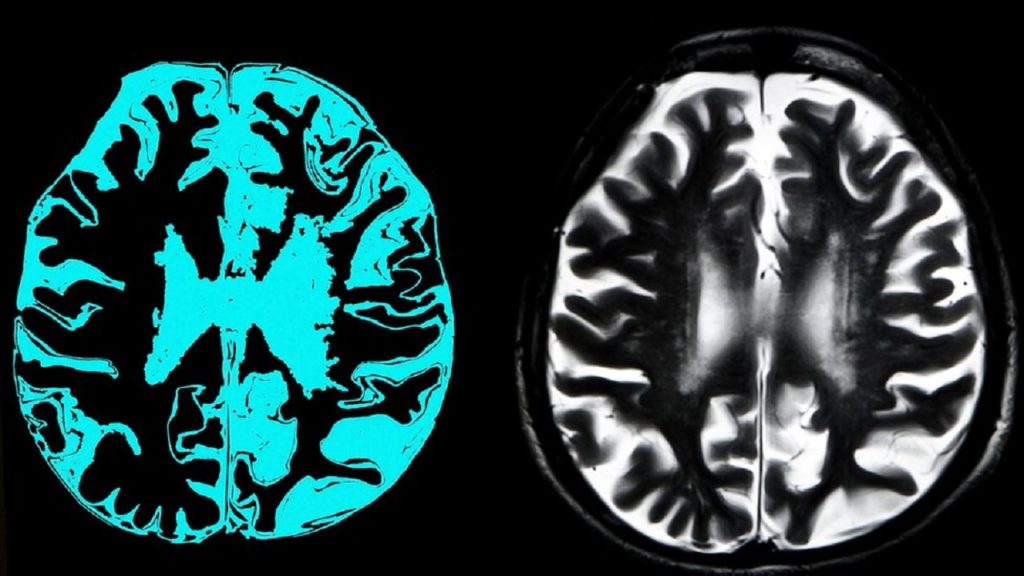

এক বিবৃতিতে বলা হয়েছে, নতুন এই ওষুধটি মস্তিষ্কে আলঝেইমার সৃষ্টিকারী এক ধরনের প্রোটিন কমাতে সক্ষম।